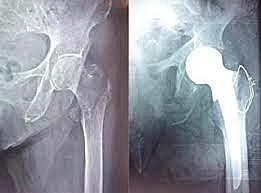

La artroplastia de Thompson ha sido una de las más utilizadas en el tratamiento de las fracturas intracapsulares de la extremidad proximal del fémur y aún hoy día se sigue implantando; en ella el tallo, a diferencia de la prótesis de Moore, es macizo y curvo, precisando para su fijación, la utilización de cemento óseo.

Usando abordaje Watson Jones ( Se secciona longitudinalmente la fascia lata por debajo del trocanter)

Las prótesis de Moore y Thompson tuvieron malos resultados debido a la erosión cotiloidea producida por la cabeza metálica

John Charnley abrió el camino para que la sustitución total de cadera fuera una técnica útil, realizada por cirujanos ortopedas bien formados, en cualquier parte del mundo.

Charnley redujo de forma considerable el diámetro de la cúpula en el vástago femoral hasta un diámetro de 22 mm para mejorar la torque de fricción. Muller siguió la idea aportando un diseño donde el diámetro de la cúpula femoral era de 32 mm.

Sir John Charnley de Inglaterra ha recibido el reconocimiento de ser el primero en utilizar exitosamente cemento oseo.

El mismo sirvió para fijar firmemente la cadera artificial al hueso y aumentó el nivel de disminución del dolor. (Los primeros diseños tenían una superficie lisa y se insertaban directamente en el hueso sin uso de cemento oseo. Esos pacientes experimentaban frecuentemente un nivel de dolor continuo luego de la inserción.)